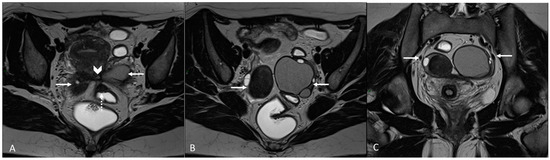

In order to perform a correct evaluation, the bladder must be at a degree of repletion suitable for the correct study of its walls and its lumen: those nodules or masses are responsible for the loss of the normal hypointense signal of the muscularis layer on T2WI. Hemorrhagic content may also be seen as hyperintense foci on T1WI, and it is also possible to observe hyperintense cystic areas on T2WI [7,14] (Figure 1).

Figure 1.

Localization of endometriosis in the vesico-uterine pouch in a 42-year-old female. (A) Sagittal T2WI (black arrow); (B) Sagittal fat-suppressed T1WI (white arrow); (C) Coronal T2WI (black arrow).

In the case of a mural mass protruding into the lumen, mucosal or submucosal edema is well depicted on T2WI [40].